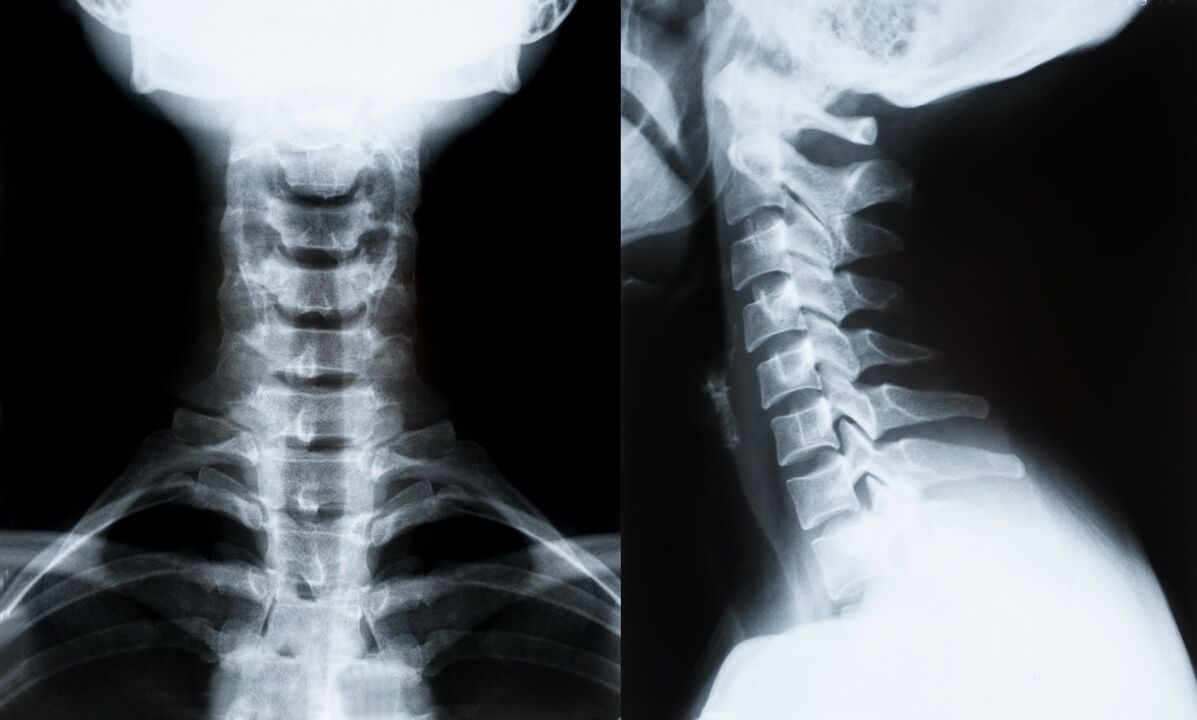

Οι κύριες μέθοδοι για τη διάγνωση και τον περαιτέρω προσδιορισμό της θεραπείας της οστεοχόνδρωσης της αυχενικής μοίρας της σπονδυλικής στήλης:

- Ρέντγκεν. Η λιγότερο αποτελεσματική, αλλά παραδοσιακή διαγνωστική μέθοδος.

- Η μαγνητική τομογραφία είναι η πιο αποτελεσματική διαγνωστική μέθοδος. Με αυτό το είδος εξέτασης του ασθενούς, όλες οι απαραίτητες δομές είναι ορατές.

- Εάν χρειάζεται να μετρηθούν οι αλλαγές, χρησιμοποιείται τομογραφία υπολογιστή. Προσδιορίζει την παρουσία κηλών και άλλων πραγμάτων.

- Η τελευταία μέθοδος είναι η υπερηχογραφική διπλή εξέταση. Αυτή η ερευνητική μέθοδος καθορίζει την ταχύτητα της ροής του αίματος στις αρτηρίες.

Είναι αδύνατο να προσδιοριστεί με ακρίβεια μια ασθένεια της σπονδυλικής στήλης στο σπίτι.